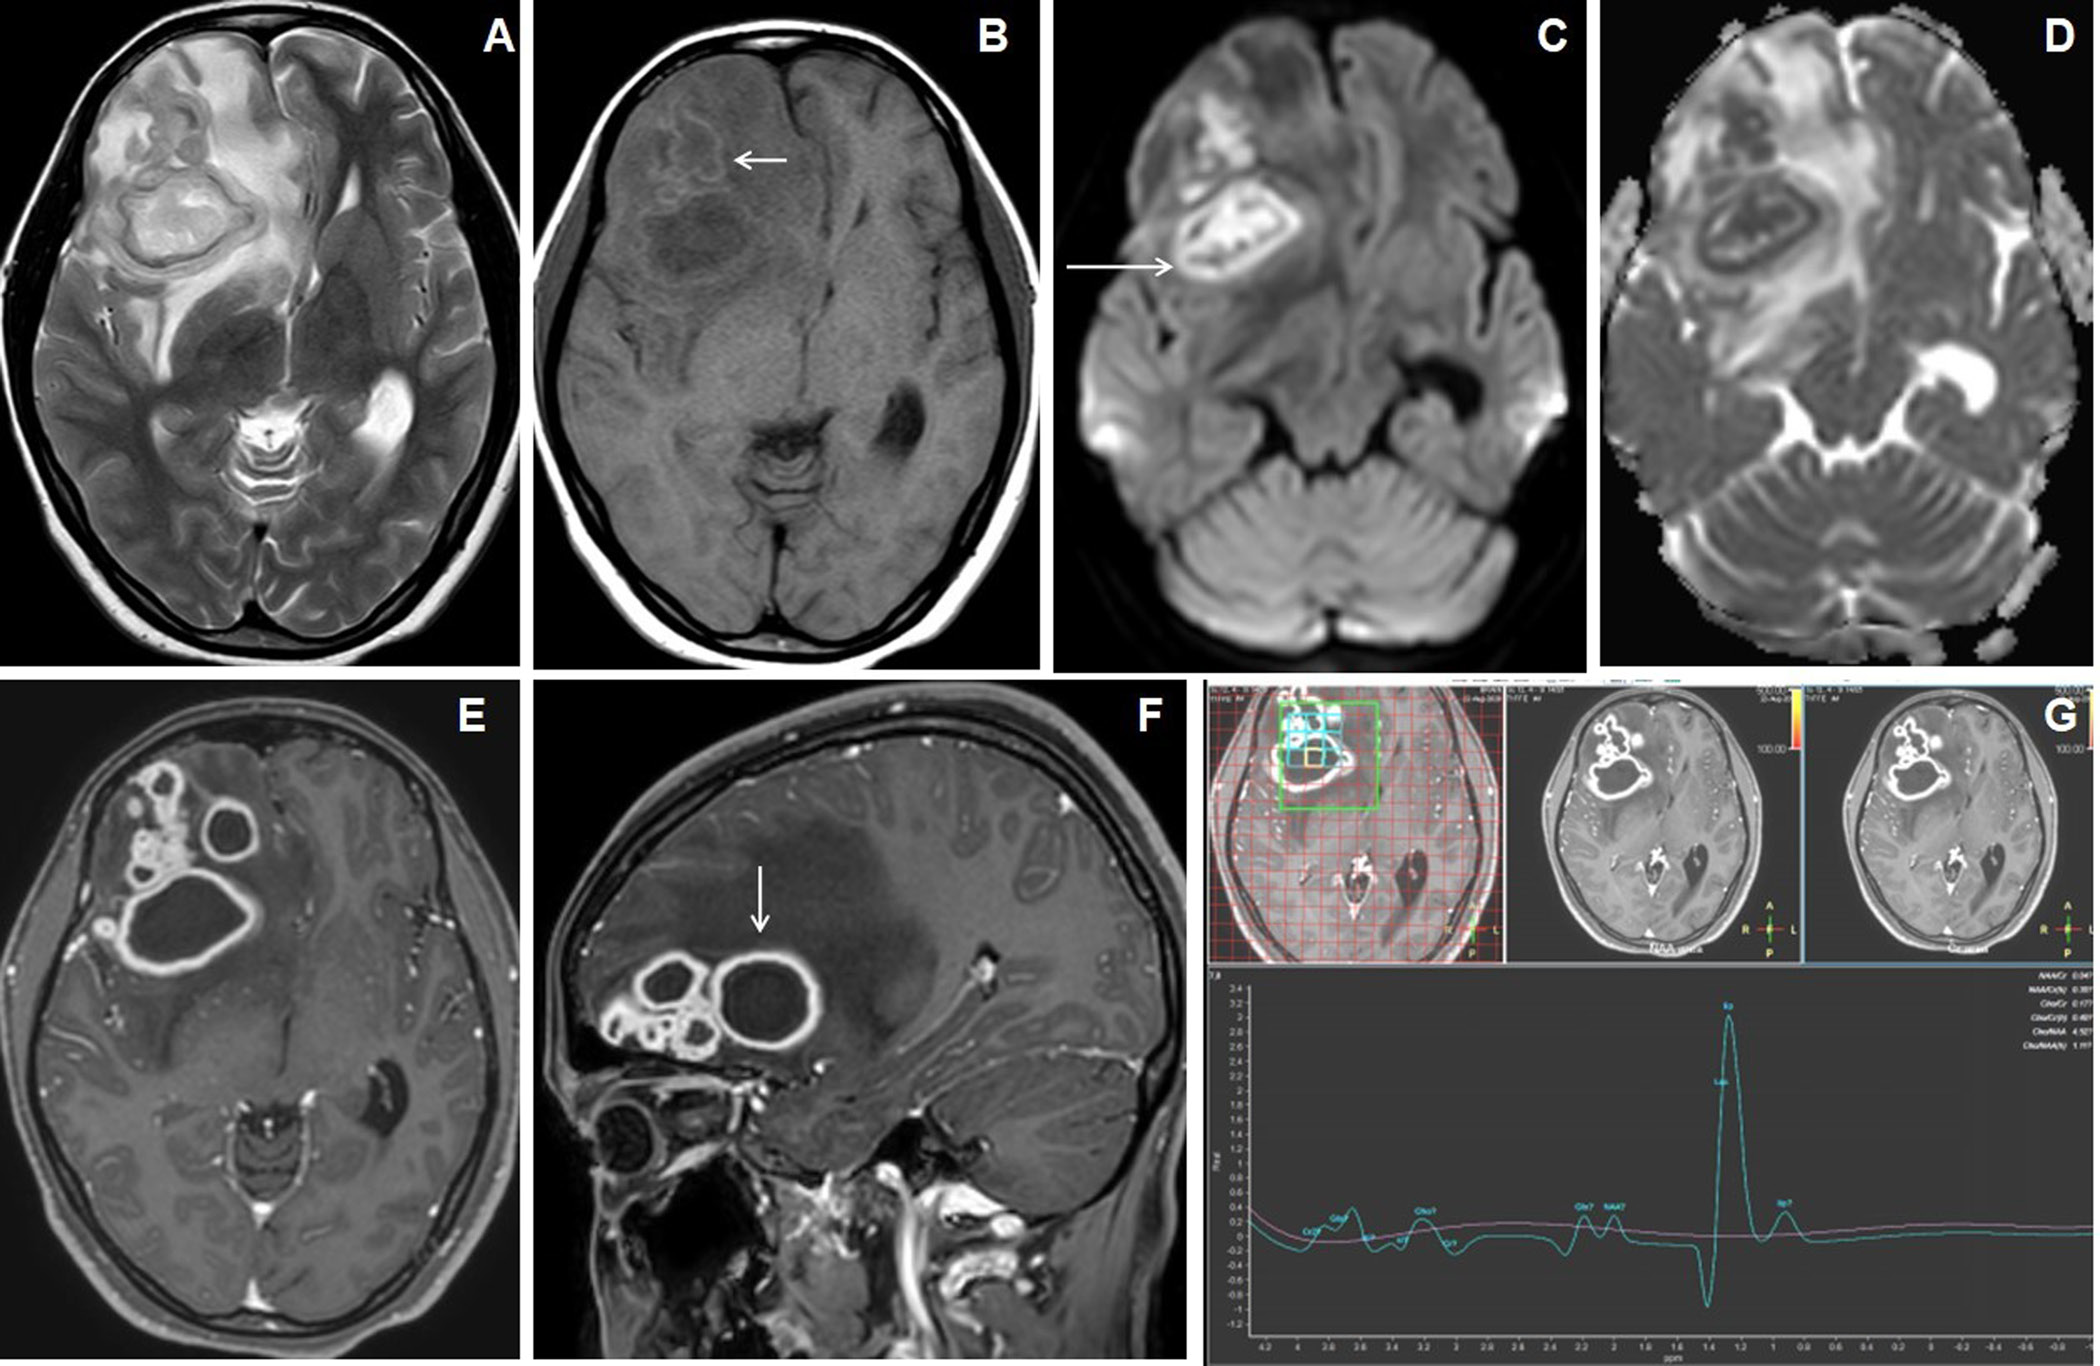

Figure 5. 13 years male presentedwith headache, vomiting and chronic backache. Cranial MRI with axial T2W image of the brain (A) shows hypointense nodular lesions in right cerebellum with perifocal edema. Axial post-contrast image (B) shows a larger irregular shaggy peripherally enhancing rim-like lesion with central necrosis (arrow) and adjacent laterally located solid nodular enhancing satellite lesion. MR spectroscopy (TE 144) image (C) shows lipid peak in 1.3ppm with slightly raised choline peak. The sagittal STIR image of spine (D) shows abnormal STIR hyperintensities in multiple lower cervical and dorsal vertebrae with partial collapse of the D5, D6 and D9 vertebrae and associated T2 hyperintense long segmental prevertebral collection in the cervico-dorsal region (arrow).